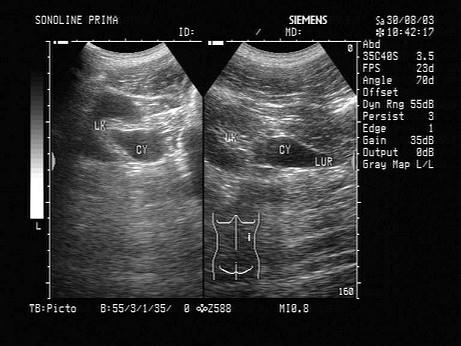

问题 超声检查如图所示,该病例最可能诊断?(?)

选项 A.肾外肾盂扩张 B.肾积水 C.输尿管上段积水 D.肾盂输尿管狭窄 E.输尿管畸形

答案 A